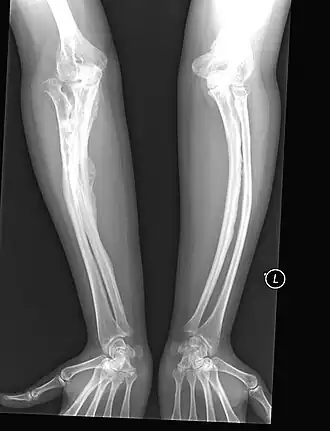

Osteogenesis imperfecta[3] (OI) of brozebottenziekte is een zeldzame, aangeboren en erfelijke bindweefselaandoening, die met name gekenmerkt is door zeer broze botten. Door een genmutatie is de hoeveelheid en/of de samenstelling van het collageen type 1 (meestal) afwijkend.

OI wordt vooral gekenmerkt door een verminderde stevigheid van de botten. Hierdoor kunnen gemakkelijk botbreuken (fracturen) ontstaan en vergroeiingen (deformaties) van de armen, benen, wervelkolom, borstkas en/of de schedel. Tevens kunnen de gewrichten overbeweeglijk (hyperlaxiteit) zijn. In sommige gevallen is ook het gebit aangetast, waarbij men spreek over dentinogenesis imperfecta. Daarnaast komen diverse nevenverschijnselen voor als blauw sclera (oogwit), bolle (enigszins uitpuilende) ogen (exophthalmus) en doofheid. Andere klachten kunnen zijn: vermoeidheid, pijn en/of overmatige transpiratie. Blauwe plekken en bloedneuzen treden eveneens gemakkelijk op. De symptomen kunnen tussen patiënten zeer verschillend in aard en in ernst zijn.

De diagnose wordt gesteld aan de hand van de bovengenoemde symptomen. Opvallend is dat baby's met ernstigere typen OI vaak al met gebroken botten geboren worden. Ook hebben patiënten vaak al op jonge leeftijd meerdere botbreuken opgelopen. Radiologisch onderzoek kan de diagnose bevestigen. Daarnaast is er genetisch onderzoek mogelijk om de diagnose met zekerheid vast te stellen en de exacte genmutatie te achterhalen.

Type III Ernstig Dit type kan al voor de geboorte breuken geven. Patiënten hebben vaak wel een normale levensverwachting, maar met langzaam progressieve verschijnselen en misvormingen.